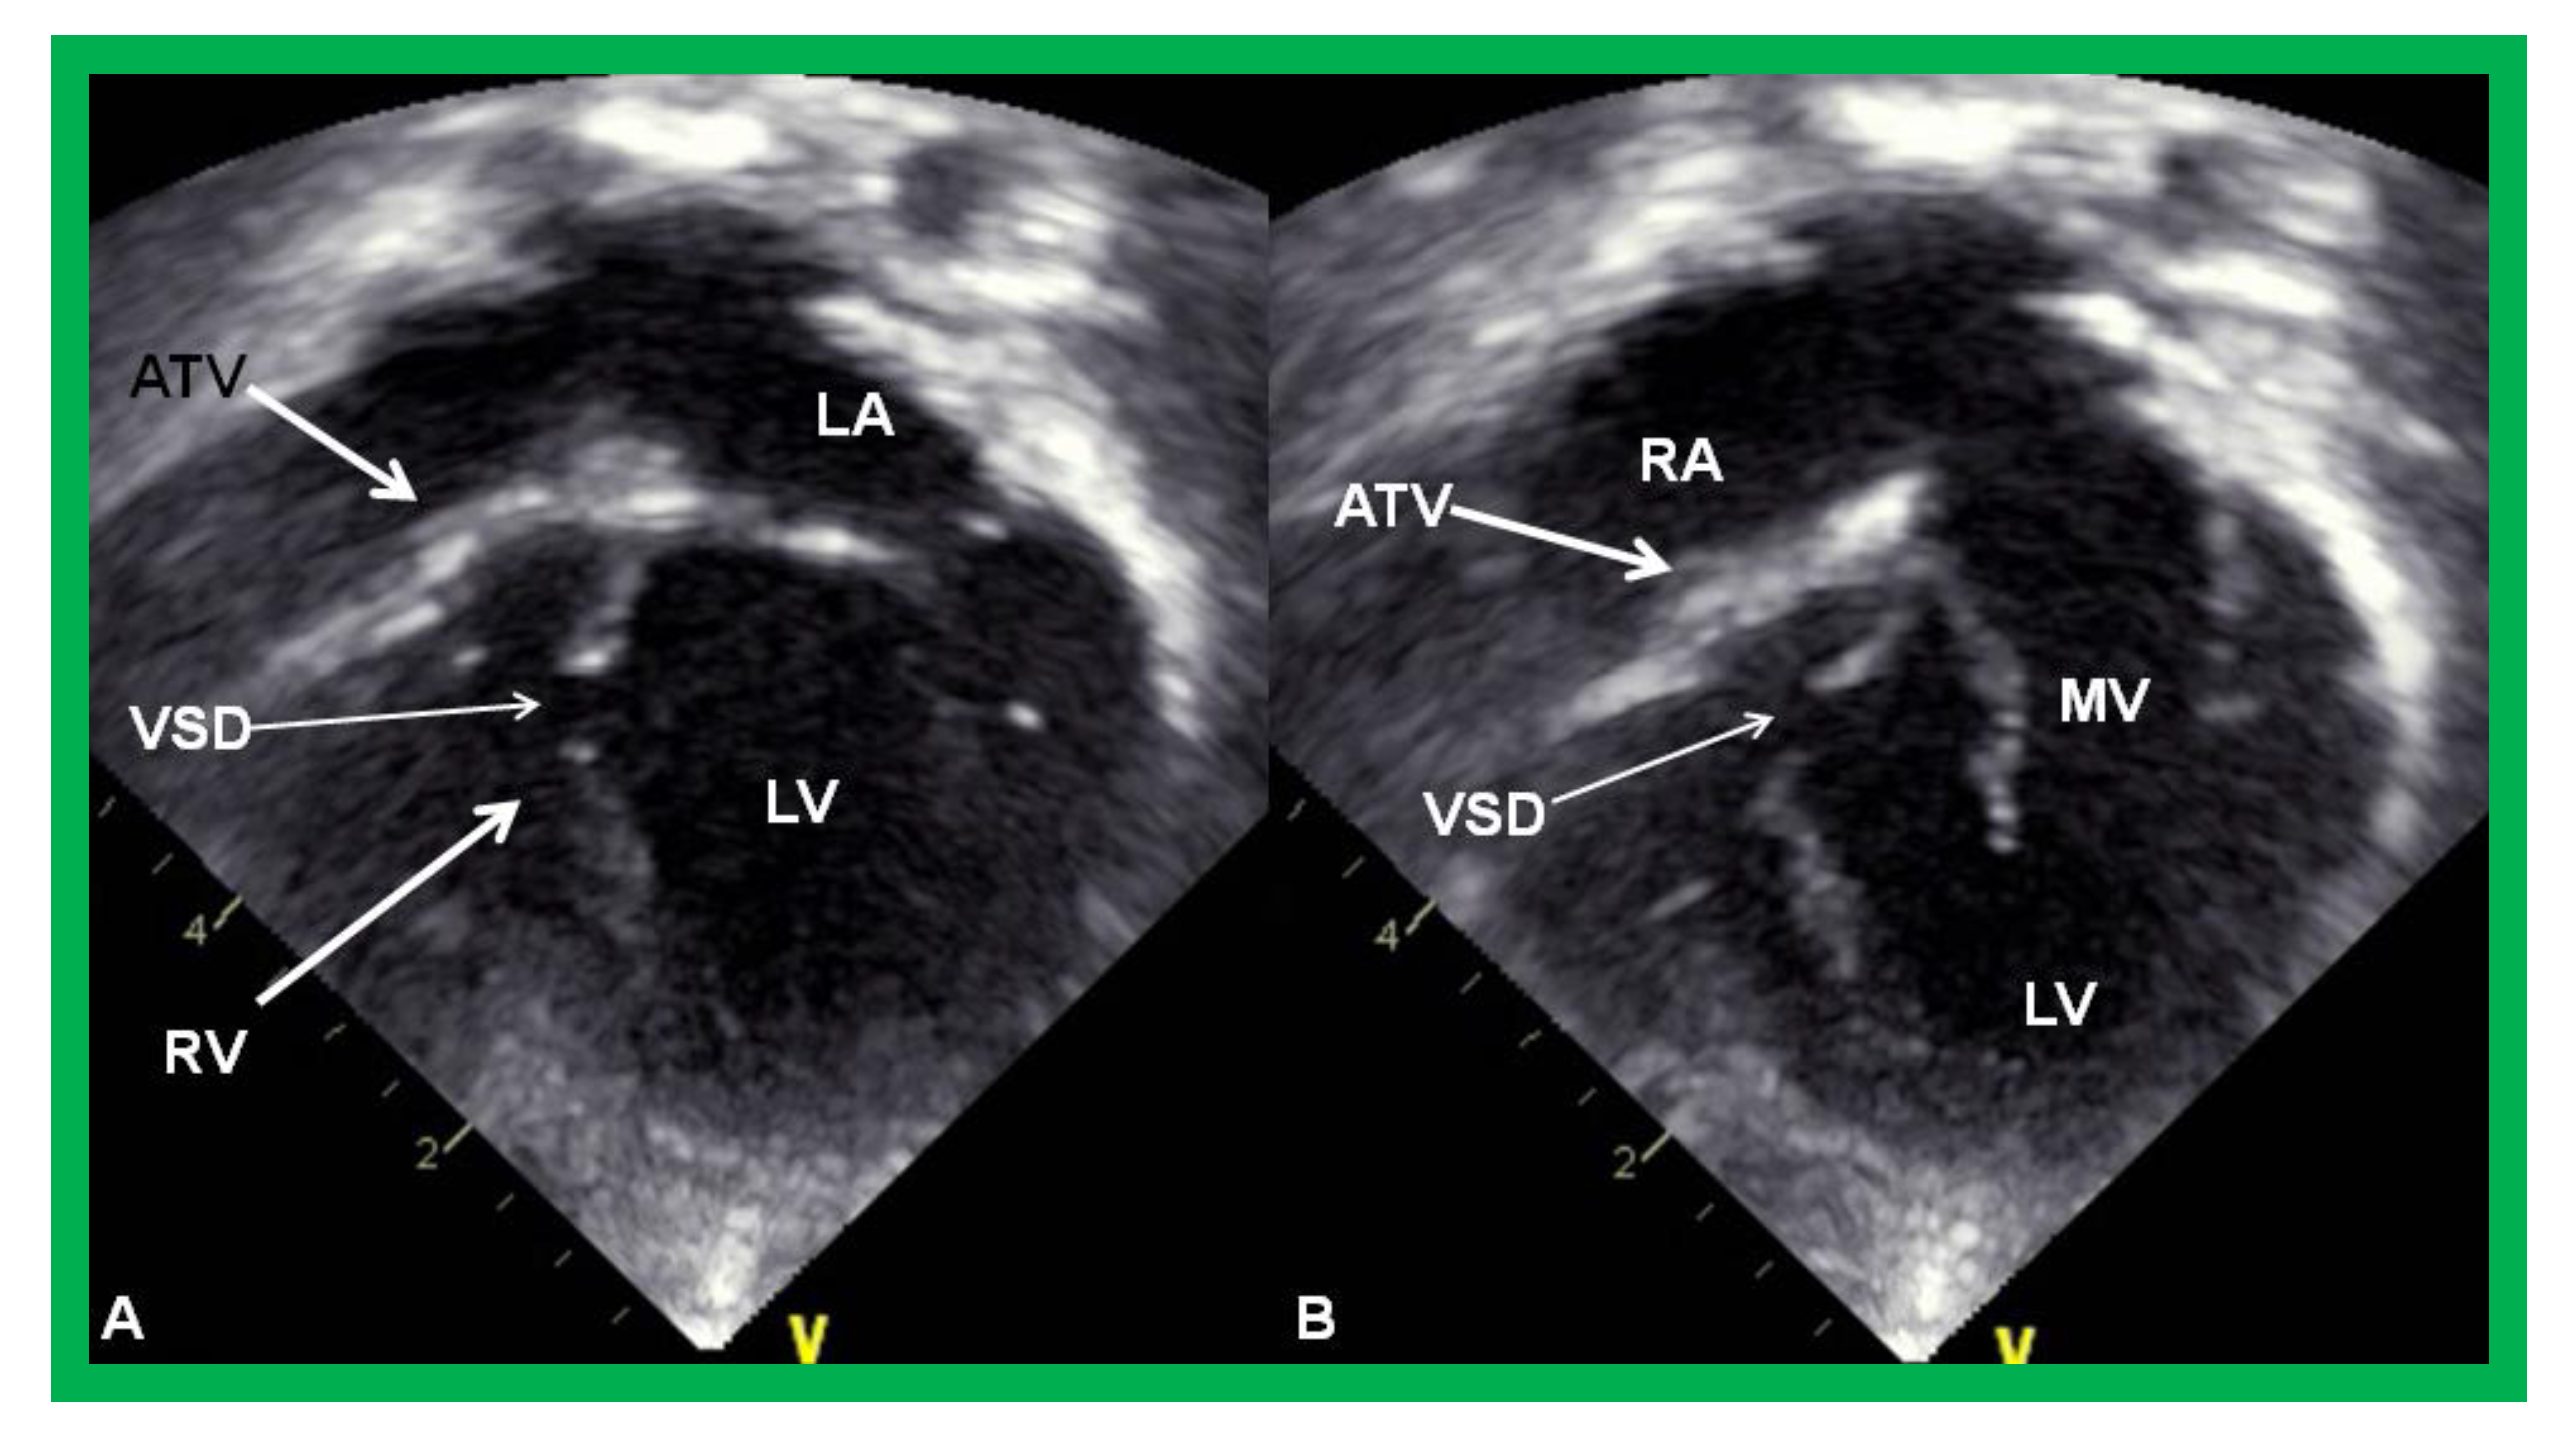

2.4. Unbalanced Atrioventricular Septal Defect